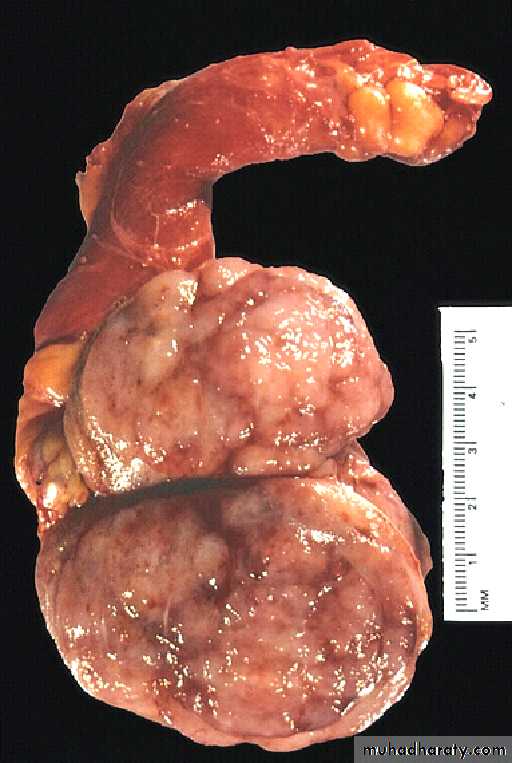

Seminoma testis gross

A small rim of remaining normal testis appears at the far right. The tumor is composed of lobulated soft tan to brown tissue.Histologically: solid nest of proliferating tumor cells in between there is randomly scattered thin fibrovascular trabeculea. The tumor cells have well defined borders with clear cytoplasm. The nuclei show limited pleomorphism and coarse granular chromatine. Typically there is lymphocytic infiltration is present in the fibrovascular trabeculea. Radiotherapy results in 5- years’ survival in 85-90%.

Classic seminoma:- about 90% of all seminomas. On gross examination, the tumor is solid, gray-white, poorly demarcated growth that bulges from the cut surface of the testis. The tumor may replace the entire testis in more than half of the cases. Histologically: solid nest of proliferating tumor cells in between there is randomly scattered thin fibrovascular trabeculea. The tumor cells have well defined borders with clear cytoplasm. The nuclei show limited pleomorphism and coarse granular chromatine. Typically there is lymphocytic infiltration is present in the fibrovascular trabeculea. Radiotherapy results in 5- years’ survival in 85-90%.